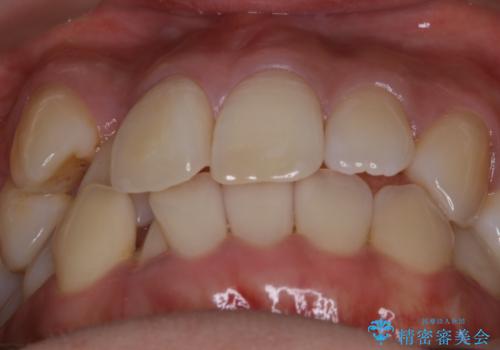

【非抜歯】インビザライン 隠れた前歯を並べる矯正治療

- 前歯のガタつき・奥に隠れてしまっている歯の矯正治療を希望されて初診来院されました。

顔貌的に口元を下げたいといった希望はなく抜歯はなるべく避けたいとのご要望からマウスピース装置(インビザライン)での治療を行うこととなりました。

非抜歯で矯正を行う場合にガタつきの改善に必要なスペースを作るために歯の遠心移動を行います。

最初の位置から奥に歯を移動させていくことで前歯のガタつきを改善したり、前歯の位置を後方に移動させることが可能となります。